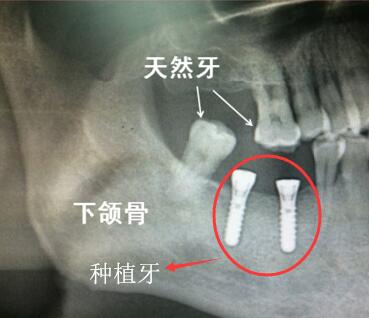

真牙和種植牙

紅圈內(nei) 為(wei) 兩(liang) 顆種植牙,上麵的兩(liang) 個(ge) 白色箭頭所指為(wei) 真牙